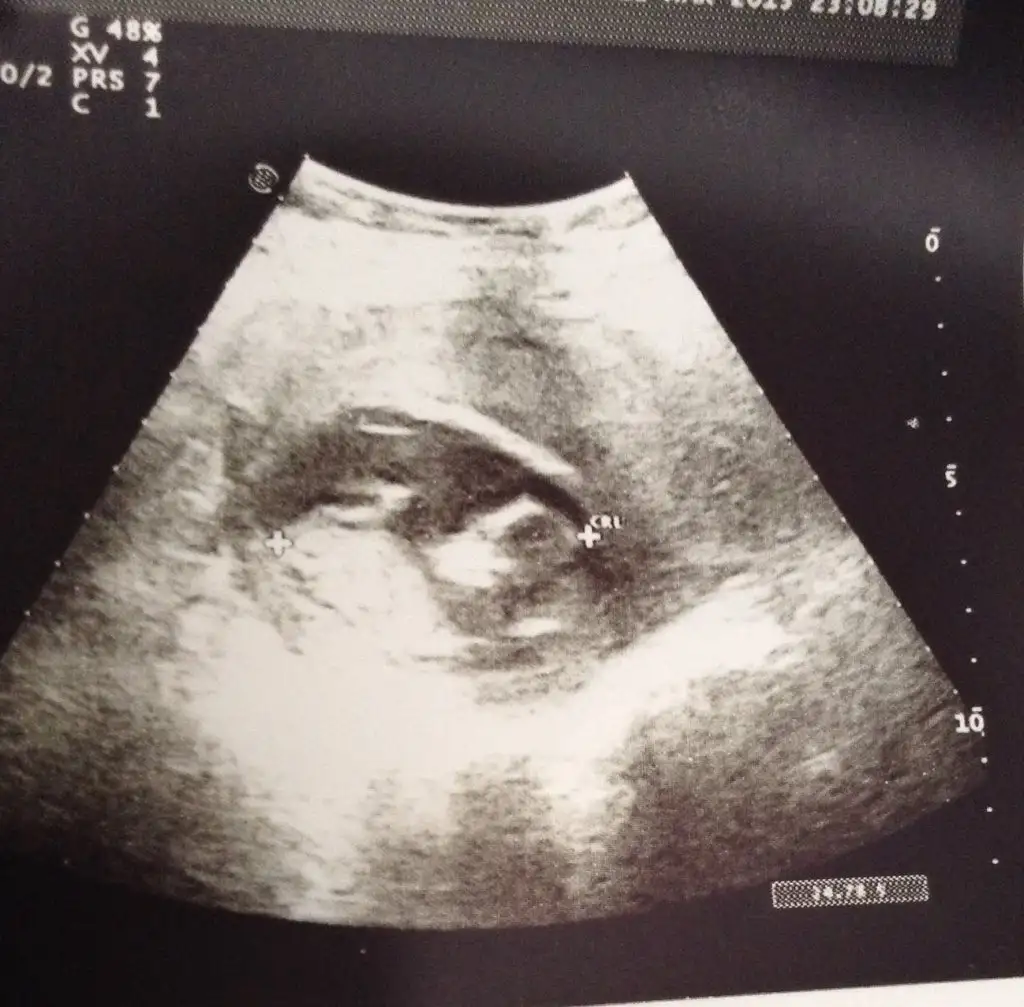

11 hafta 5 günlük 5.1 cm. Haftasina göre uyumlu ama cinsiyet için mi diyorsun?Canim haftasina gore kucuk deilmi 11 cm mi ?? Kiz gibi geldi ...

Ben 23 haftalik gordum sanki.. ozman normal tabu. Canim ben kiz gibi gordum .. sen nne hissediyorsun etraftan ne diyolar :)ozgebask post: 39938161 .!.:11 hafta 5 günlük 5.1 cm. Haftasina göre uyumlu ama cinsiyet için mi diyorsun?